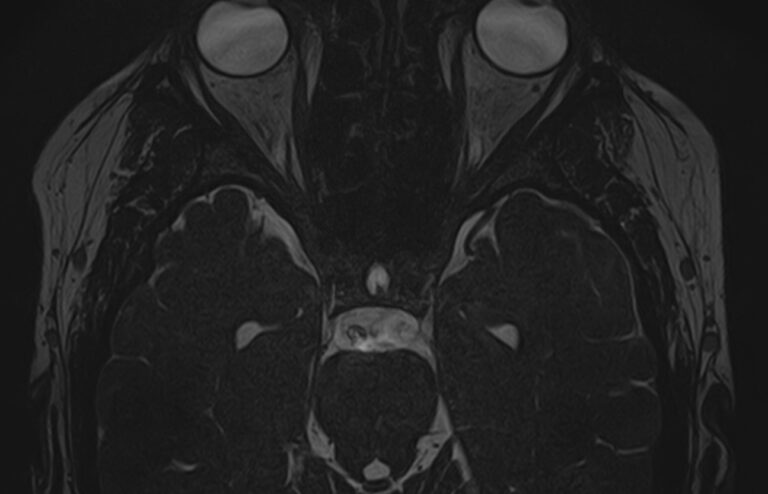

Для диагностики поражения черепно-мозговых нервов, а также оценки состояния окружающих их тканей и визуализации сосудистой сети головного мозга в клинике «Доступная медицина» проводится комплексное обследование МРТ головного мозга + Мр-ангиография головного мозга + МР-венография головного мозга + черепно-мозговые нервы. Данное обследование включает в себя несколько протоколов: стандартный – для оценки состояния всех структур головного мозга и дополнительные – для изучения очагов поражения черепных нервов и визуализации всей сосудистой системы головного мозга.

Исследования выполняются на современном высокопольном томографе экспертного класса TOSHIBA VANTAGE TITAN 1,5 Тесла, который использует разные режимы сканирования с толщиной среза от 1мм в различных плоскостях с последующей цифровой обработкой полученных данных для создания трехмерных изображений. МР-ангиография отображает состояние артериальной системы кровоснабжения головного мозга. МР-венография головного мозга позволяет детально изучить особенности венозного русла головного мозга.

Данное комплексное исследование в большинстве случаев проводится с контрастным усилением, которое необходимо для улучшения визуализации черепно-мозговых нервов. Для этого внутривенно вводится препарат, содержащий гадодиамид (соли металла гадолиния) для получения изображений с высокой четкостью и контрастностью, что способствует ранней диагностике заболеваний головного мозга.

В головном мозге берет начало 12 пар черепно-мозговых нервов. К ним относятся обонятельный нерв, зрительный, тройничный, лицевой, преддверно-улитковый, блуждающий и др. Название нерва, как правило, отражает его функцию или соответствует органу, который он иннервирует.

Часто поражение черепных нервов обусловлено патологией близлежащих тканей головного мозга или связано с проблемами расположенных рядом сосудов. Поэтому целесообразно проведение комплексного исследования с оценкой всех структур головного мозга, включая сосудистую систему.